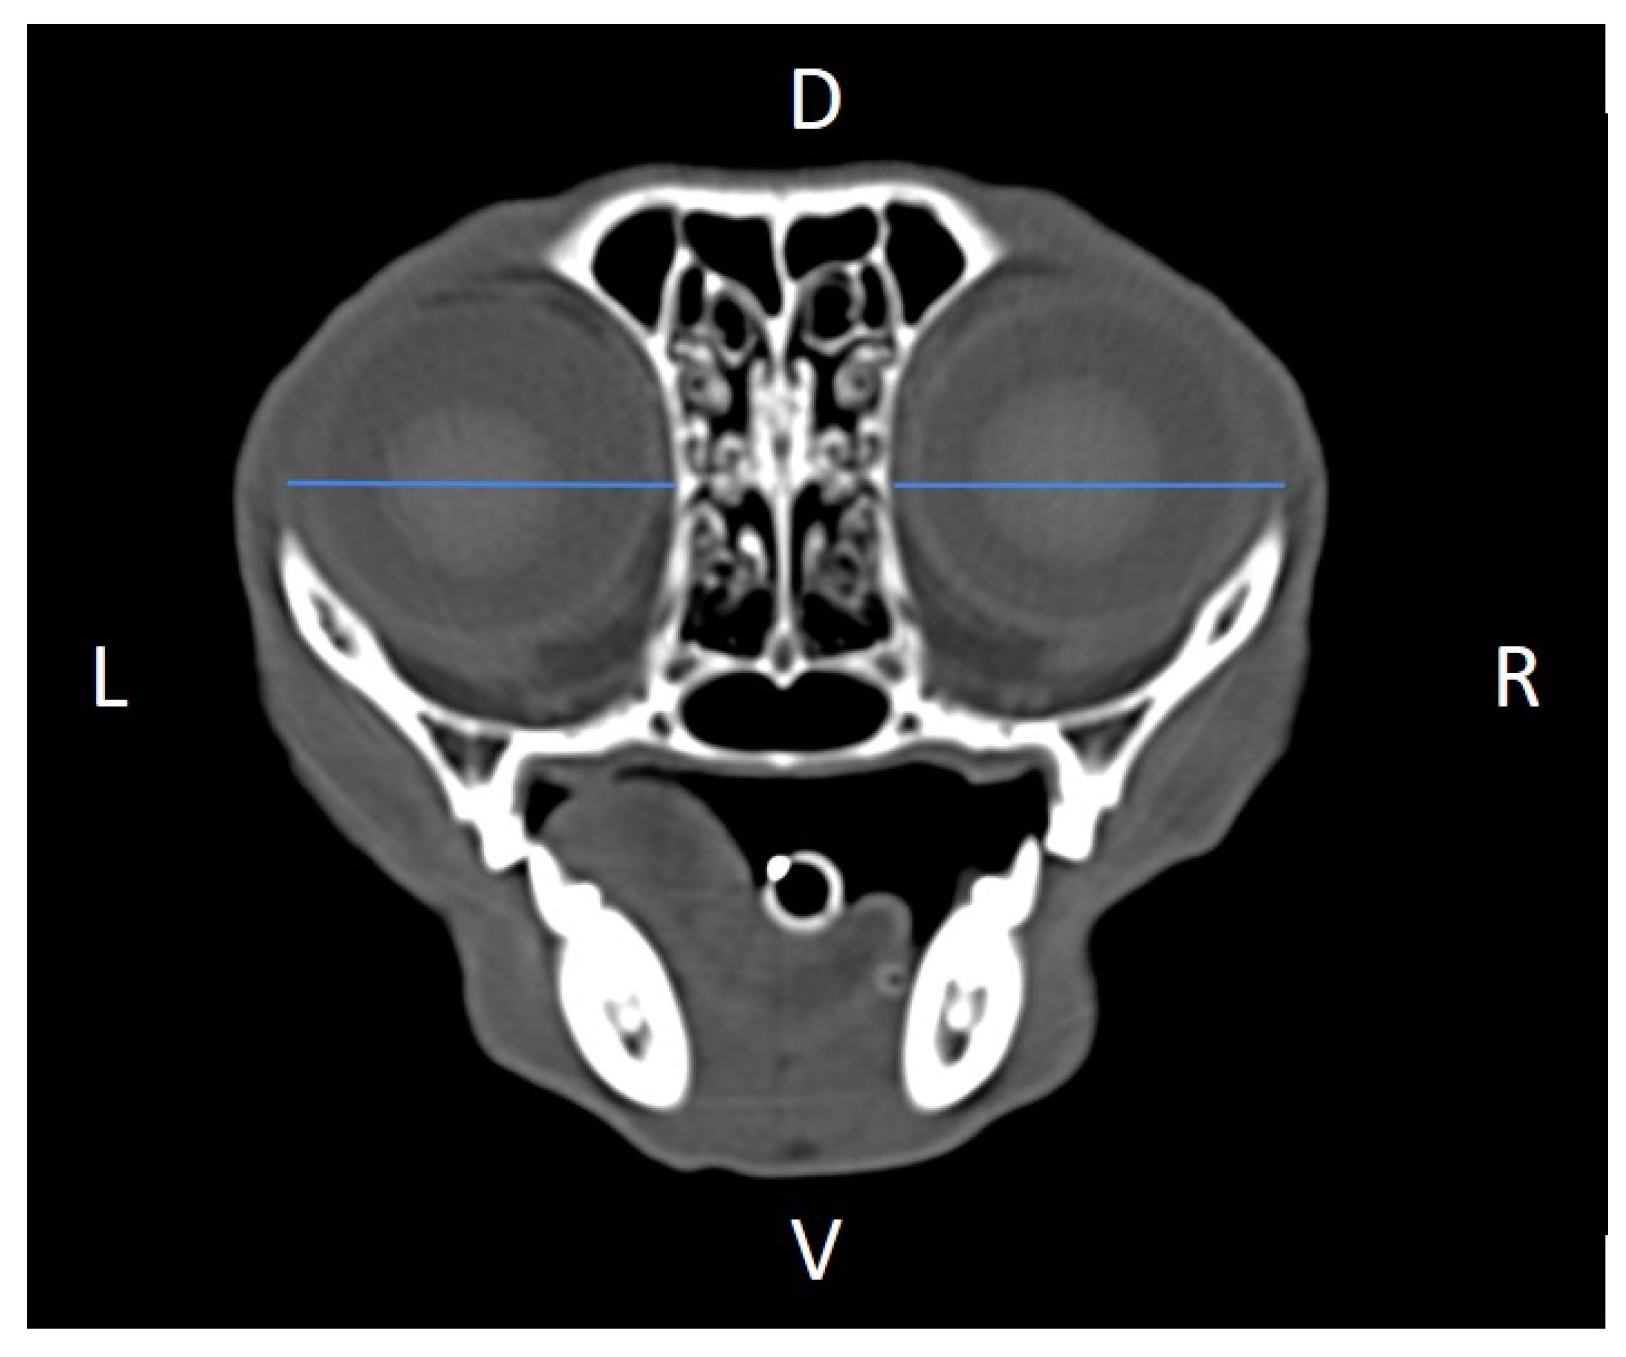

In order to perform the linear measurements described in Table 1, firstly, rotational misalignment of the head was corrected by aligning the images in the three planes, as demonstrated in Figure 1. The sagittal plane (Figure 1A) was aligned at the level of the nasal septum and the interincisive midline; the transverse plane (Figure 1B) was oriented perpendicular to the hard palate; and the dorsal plane (Figure 1C) was parallel to the hard palate. Since the computer program used allowed for the simultaneous visualization of the three anatomical planes (sagittal, transverse, and dorsal), the identification of the measurement planes and the delimitation of the anatomical structures to be measured was performed with greater precision.

Figure 1. Representative multiplanar computed tomography reconstruction showing the sagittal (A), transverse (B), and dorsal (C) planes. The sagittal plane was aligned at the level of the nasal septum and the interincisive midline; the transverse plane was oriented perpendicular to the hard palate; and the dorsal plane was parallel to the hard palate. D, dorsal, L, left, R, right, Ro, rostral, V, ventral.